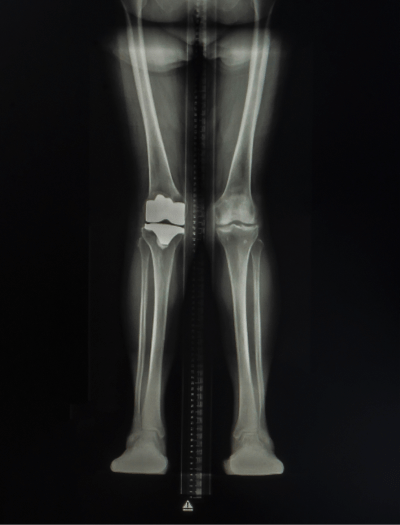

Femur fracture

age 13

Metatarsal fracture

age 16

Tibial fracture

age 57